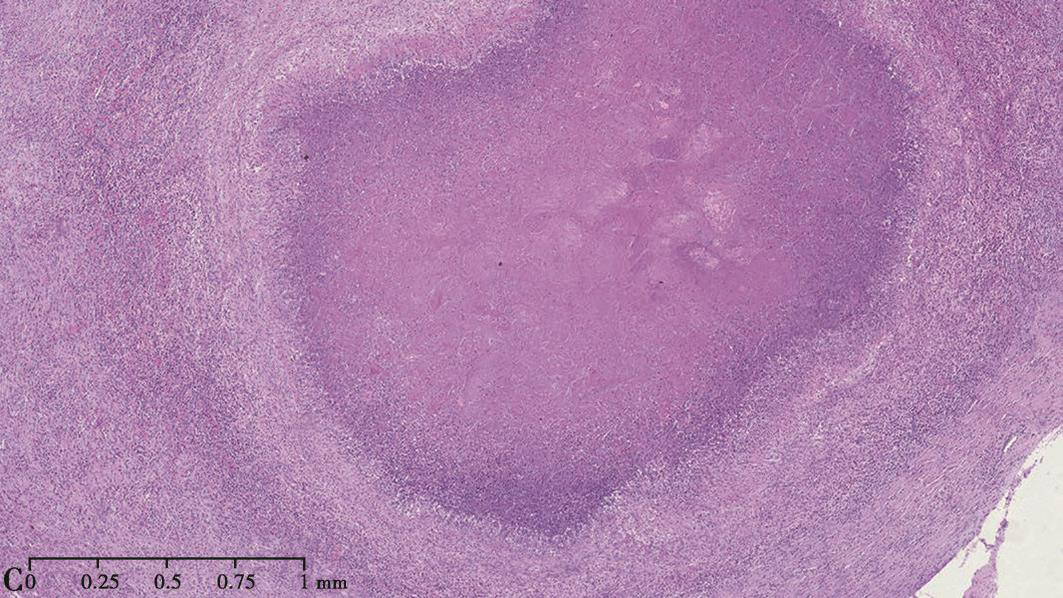

【组织病理结果】

病例Ⅰ:外院(2013年2月7日)左下肺结节穿刺活检示肉芽肿性炎伴坏死(图3A),PAS及抗酸染色阴性。穿刺组织培养发现呈双相生长的真菌,证实为组织胞浆菌,同时组织匀浆涂片GMS染色见组织胞浆菌孢子。

病例Ⅱ:手术标本可见病灶呈硬结改变,边界清楚,剖面呈鱼肉样改变,伴中心坏死(图3B);病理检查示肉芽肿性结节,伴凝固性坏死(图3C)。

图3病例I、Ⅱ肺组织病理表现

病例Ⅰ:肺穿刺活检标本病理可见肉芽肿样结节病变,伴凝固性坏死(A.HE染色,100×)。病例Ⅱ:手术标本可见病灶呈硬结改变,边界清楚,剖面呈鱼肉样改变,伴中心坏死(B);病理检查示肉芽肿性结节,伴凝固性坏死(C.HE染色,50×)

肺组织胞浆菌病的肺部病理改变与含菌量及患者机体免疫状况有关,可表现为炎性渗出或肉芽肿性炎症,严重者可出现弥漫性肺泡损伤。免疫功能正常人群常表现为肉芽肿性炎症,伴或不伴有坏死,需要与其他真菌及结核性肉芽肿性炎症鉴别。肺组织特殊染色有时可以找到组织胞浆菌,呈酵母样,直径为2~5μm,可见核内深染小点及外周空晕。上述2例患者均为免疫功能正常个体,病理组织学均表现为肉芽肿性炎症伴凝固性坏死,符合组织胞浆菌的肺部病理改变,肺活检组织培养分离鉴定进一步确定为组织胞浆菌。